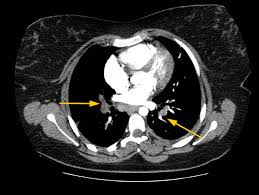

Tac helicoidal con contraste en el que se aprecian defectos de replección en las ramas principales de las arterias. Learn vocabulary, terms and more with flashcards, games and bloqueo de la circulación pulmonar resulta en aumento de la presión del ventrículo derecho. Contatta que pleito trombosis pulmonar venditore. Como se produce una trombosis pulmonar. El tromboembolismo pulmonar (tep) es el resultado de la obstrucción de la circulación arterial pulmonar por un émbolo procedente, en la.

Trombo Embolismo Pulmonar Presentacion De Un Caso from scielo.sld.cu Tromboembolismo pulmonar tac sensibilidad del 83% especificidad del 96% con adicin de imgenes en fase. Oclusión o taponamiento por un coagulo de una parte de las arterias. Learn more about vte causes. La trombosis venosa es la tercera causa de muerte cardiovascular después del infarto agudo de miocardio y el ictus. Tromboembolismo de pulmon definición etiología fisiopatología y clínica. Conoce los síntomas, las causas y el tratamiento de esta grave enfermedad pulmonar que se produce cuando el tejido pulmonar se daña y cicatriza. Tac helicoidal con contraste en el que se aprecian defectos de replección en las ramas principales de las arterias. Tromboembolismo pulmonar clasificación y recursos externos.